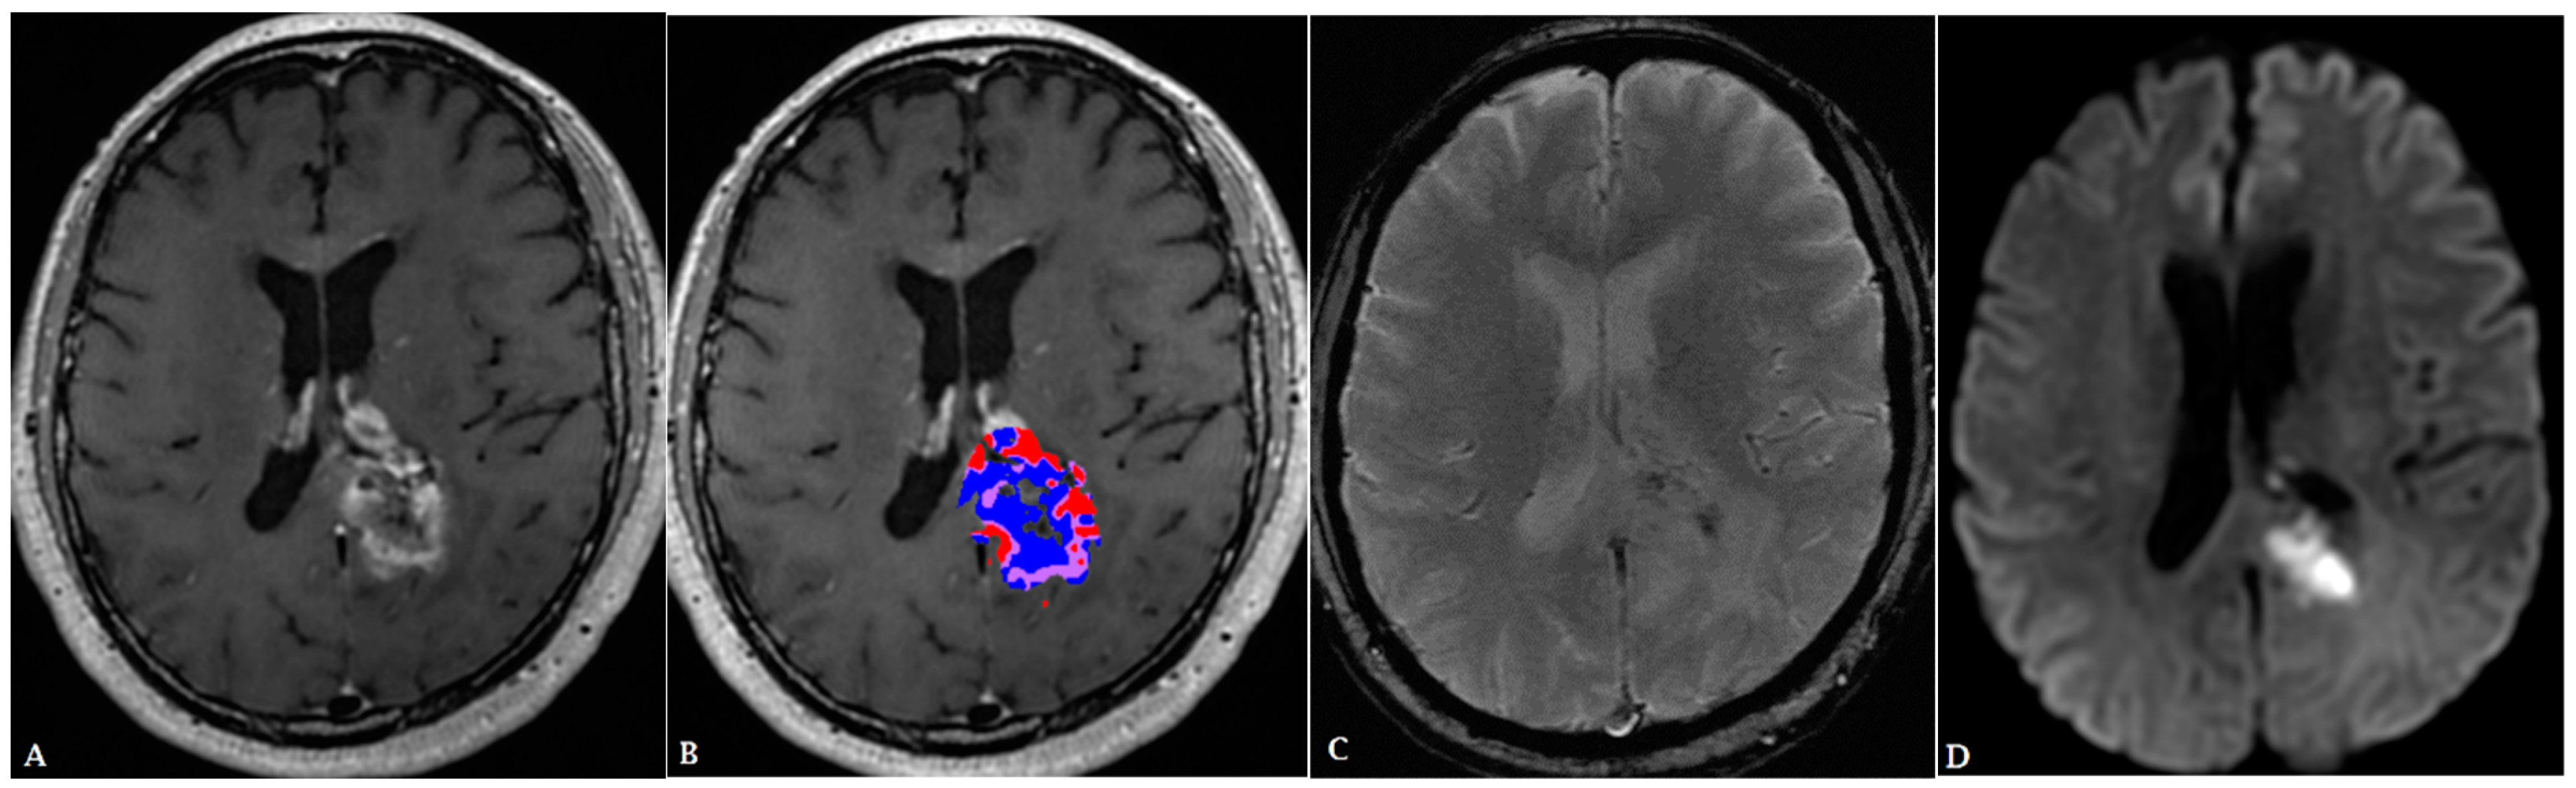

- Artzi, M.; Bressler, I.; Ben Bashat, D. Differentiation between glioblastoma, brain metastasis and subtypes using radiomics analysis. J. Magn. Reson. Imaging 2019, 50, 519–528. [Google Scholar] [CrossRef]

- Qian, Z.; Li, Y.; Wang, Y.; Li, L.; Li, R.; Wang, K.; Li, S.; Tang, K.; Zhang, C.; Fan, X.; et al. Differentiation of glioblastoma from solitary brain metastases using radiomic machine-learning classifiers. Cancer Lett. 2019, 451, 128–135. [Google Scholar] [CrossRef]

- Priya, S.; Liu, Y.; Ward, C.; Le, N.H.; Soni, N.; Pillenahalli Maheshwarappa, R.; Monga, V.; Zhang, H.; Sonka, M.; Bathla, G. Radiomic Based Machine Learning Performance for a Three Class Problem in Neuro-Oncology: Time to Test the Waters? Cancers 2021, 13, 2568. [Google Scholar] [CrossRef]

- Bathla, G.; Dhruba, D.D.; Soni, N.; Liu, Y.; Larson, N.B.; Kassmeyer, A.B.; Mohan, S.; Roberts-Wolfe, D.; Rathore, S.; Le, N.H.; et al. AI-based classification of three common malignant tumors in neuro-oncology: A multi-institutional comparison of machine learning and deep learning methods. J. Neuroradiol. 2023. [Google Scholar] [CrossRef] [PubMed]